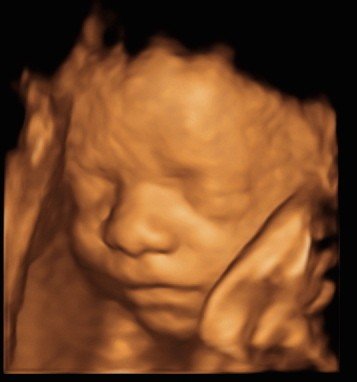

View beautiful baby scan images captured in our studios

Baby scan image 4